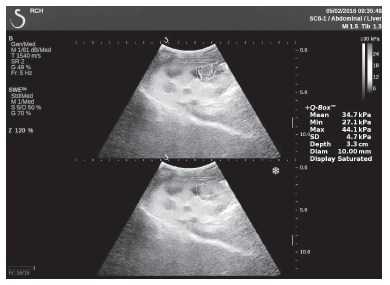

Клинический пример из первой группы. Пациент М., с хронической почечной недостаточностью. Трансплантация почки произведена от живого родственного донора. Трансплантат находится в правой подвздошной области. При нормальном функциональном состоянии трансплантата, показатели цветовой и спектральной допплерографии оценивались как удовлетворительные, с индексом резистентности не более 0,60 (рис. 1); показатели жесткости паренхимы почечного трансплантата при УЭСВ на различных участках составили от 20,05 до 29,18 кПа (рис. 2-4).

Рисунок 3. Исследование в режиме ультразвуковой эластографии сдвиговой волны у пациента М.: жесткость паренхимы в зоне верхнего полюса почечного трансплантата 21,4 кПа

Рисунок 8. Исследование в режиме ультразвуковой эластографии сдвиговой волны у пациента К.: жесткость паренхимы в зоне нижнего полюса почечного трансплантата 34,7 кПа